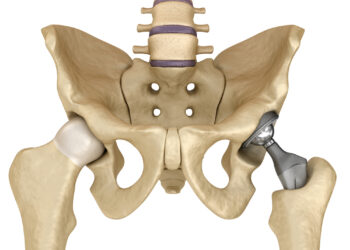

Skaityti daugiauDetailsKlubo artritas – tai būklė, kai sąnario kremzlė, kurios pagrindinė užduotis yra apsaugoti ir paminkštinti sąnarį, pradeda dėvėtis arba uždegti....

Skaityti daugiauDetailsKlubo impingementas – tai būklė, kai klubo sąnario kaulai nesusijungia sklandžiai, todėl jie trina vienas kitą ir sukelia diskomfortą ar...